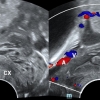

首例血管覆膜支架置入术解决血透患者反复动静脉内瘘狭窄

血透中心 张菡 文静